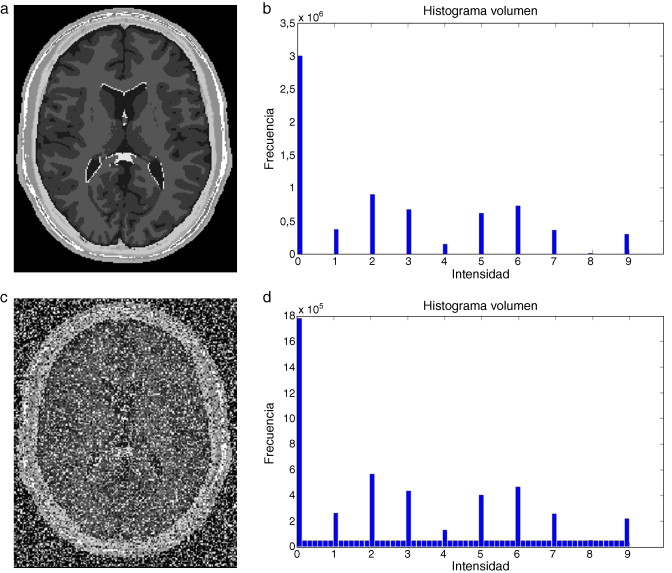

En la figura 4 , se muestra un ejemplo de ruido aditivo al agregar ruido aditivo del tipo Gaussiano a una imagen de phantom de BrainWeb[15] que simula una IRM del cerebro. El comportamiento del ruido agregado puede ser observado en el histograma de la figura (4.d).

|

|

|

Figura 4. Adición de ruido aditivo a imágen de phantom de IRM del cerebro. (a) Corte axial 98 de phantom original. (b) Histograma de (a). (c) Imagen original (a) con ruido aditivo gaussiano . (d) Histograma de (c). |

En la figura 5 es presentado un ejemplo de ruido multiplicativo agregado a la imagen de phantom que simula una resonancia magnética del cerebro. El comportamiento del ruido agregado puede ser observado en el histograma de la figura (2.d).

|

|

|

Figura 5. Adición de ruido multiplicativo a imágen de phantom de IRM del cerebro. (a) Corte axial 98 de phantom original. (b) Histograma de (a). (c) Imagen original (a) con ruido multiplicativo. (d) Histograma de (c). |